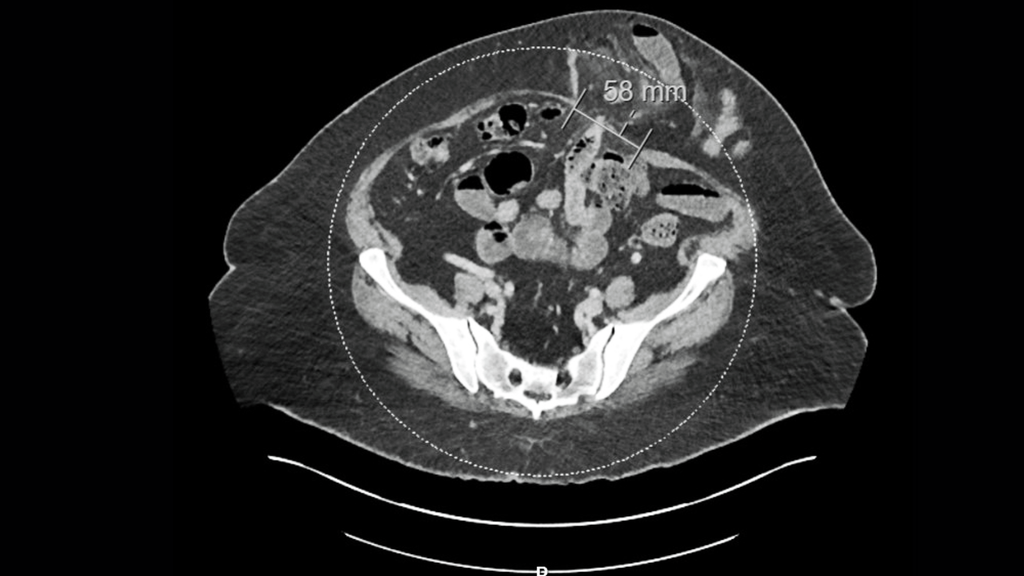

CT scan showing a large recurrent ventral hernia containing multiple loops of bowel

Figure 1: CT scan showing a large recurrent ventral hernia containing multiple loops of bowel.

At admission, she had a BMI of 38, hypertension, and bullous pemphigoid. Her medical history included a total abdominal hysterectomy and other abdominal surgeries, including the source of her present pain, a previous left lateral ventral hernia repair at an outside hospital. A CT scan at this time (Figure 1) showed a large recurrent ventral (incisional) hernia containing multiple loops of bowel.